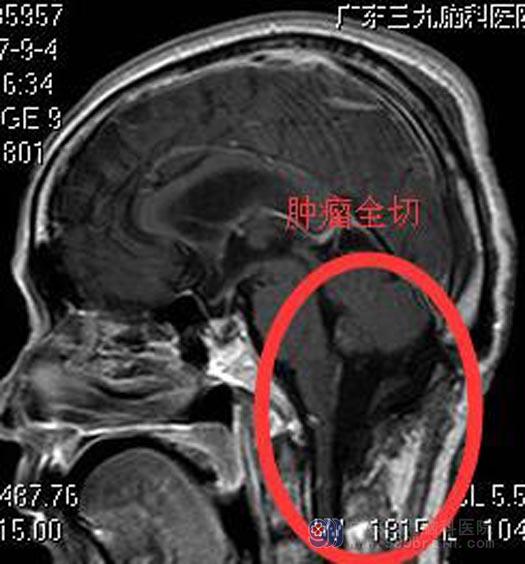

人的呼吸中枢和心血管中枢在脑干延髓中,手术稍有不慎损伤到中枢就会有生命危险,手术风险很大,对医院设备和手术医生技术要求都非常高。骆先生和家属都积极要求手术治疗。由综合神经外科鲁明主任主刀,在全麻下行延髓、四脑室巨大占位切除术,术中显微镜下见灰褐色肿瘤组织,位于右侧延髓腹外侧,肿瘤质软,血供一般,肿瘤基底部与副神经、舌咽神经、迷走神经粘连紧密,予小心分离后切除,过程中副神经、舌咽神经、迷走神经、小脑后下动脉均保留完整,肿瘤全切,手术顺利。术后神志清醒,生命体征平稳,无后组颅神经损害症状。病理回报:室管膜瘤 WHO II级。